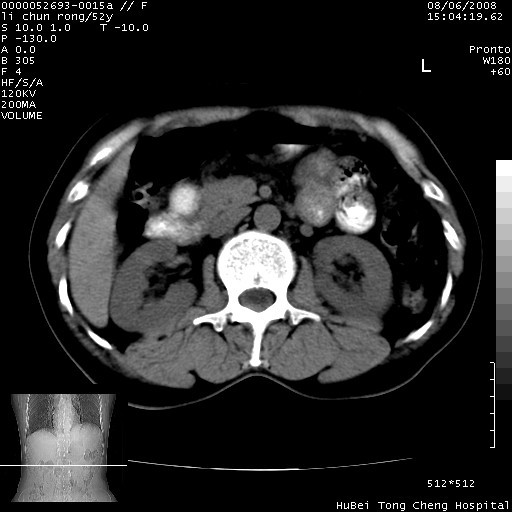

以下是引用云翔在2008-8-7 6:20:00的发言:[br]胰尾部囊性病变,考虑假囊肿,结合实验室检查疾病史

以下是引用zjzjr在2008-8-7 8:38:00的发言:[br]支持胰腺炎伴假囊肿形成,左肾小囊肿.少量腹水.

以下是引用随光逐影在2008-8-7 9:12:00的发言:[br]1)考虑胰腺炎伴假性囊肿形成可能性大;胰腺囊腺瘤待排。2)左肾小囊肿。3)少量腹水。